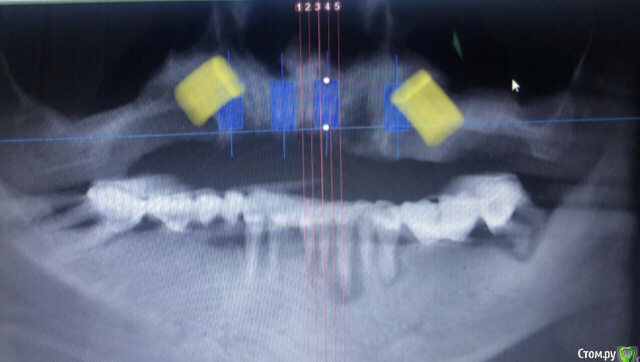

Александр07 Опубликовано 1 июля, 2020 Поделиться Опубликовано 1 июля, 2020 Коллеги доброго дня, пац 55-60 лет, хочет чтобы было красиво и крепко держалось, такая ситуация во рту, планируем операцию на вчКак видите примерно в обл 1.4-1.6 дефект по высоте, размышляю по поводу установки 1.1,1.3, 2.2,2.4 с расщеплением в обл 1.3, под протез на балке, Врем конструкция на импл , даже при условии что получится без большой подсадки, не рискнул бы- крупный мужчина, будет давать нагрузку, если ставить Мини импл то планировал бы позиции 2.1,2.5, 1 сегмент пока не ясно куда ставить ) По аугментации в обл 1.5-1.6, что посоветуете- делать /не делать, одновременно с фронтом или отдельно, или ограничиться тем планом по балке что написал выше , В обл 2.5-2.6 синус нужен trim.F286E467-8CC6-421B-ACE6-47434003E04E.MOV Ссылка на комментарий

Bier Опубликовано 1 июля, 2020 Поделиться Опубликовано 1 июля, 2020 мне не нравится вариант с расщеплением.тут нужно еще КТ покрутить 1 Ссылка на комментарий

Nazim_NV86 Опубликовано 4 июля, 2020 Поделиться Опубликовано 4 июля, 2020 (изменено) Как расположить такой винт, чтобы не соприкасался с имплантом? Таблетку под углом к импоанту?1.Типа того2.У вас ФИО пациента видно. Желательно обрезать, то что выкладываете в сеть.3.Скачайте с оф сайта планмеки нормальную бесплатную версию. Там уже 6-я версия с мая этого года. И главное что ваш нарисованный план будет сохраняться. Изменено 4 июля, 2020 пользователем Nazim_NV86 2 Ссылка на комментарий